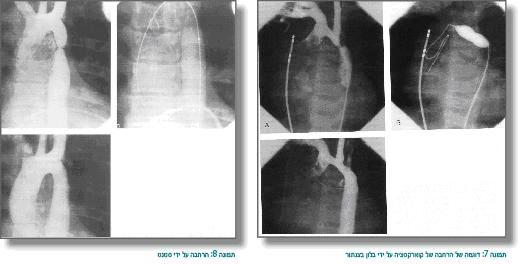

- בילד גדול יותר, המופיע לרוב בגלל אוושה, יתר-לחץ דם או דפקים פמורליים מוחלשים, יש כמה אפשרויות תיקון - ניתוח, הרחבה עם בלון בצנתור או הרחבה בצנתור על ידי השתלת תומכן (סטנט). הגישה אינה אחידה במקומות שונים, אך נהוג בשנים הראשונות לחיים לבצע ניתוח (שכיחות של היצרות חוזרת קטנה יותר בגיל הצעיר אחרי ניתוח מאשר אחרי בלון), ובגיל מאוחר יותר נהוג להרחיב עם בלון או תומכן (ובמקרים שבהם מתפתחת היצרות חוזרת אחרי ניתוח, נהוג להרחיב בהצלחה על ידי בלון, ולעתים תומכן) (תמונות 8,7).